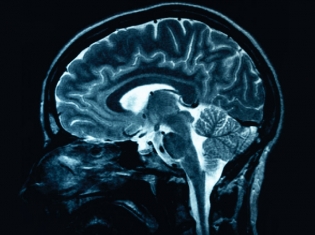

Schizophrenia is a mentally debilitating disorder characterized by delusions, disturbed thinking and lack of normal social behavior. At least half of them are not receiving appropriate care, and so finding clues that help identify the disorder could be vital.

“Our results not only open the door to a better understanding of schizophrenia,” Dr. Rouleau said, "they also give us valuable information about the molecular mechanisms involved in human brain development and function.”